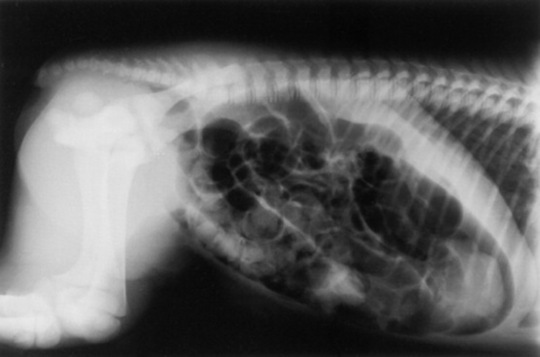

Skeletal maturity is assessed by radiographing a carpus and a tarsus for evidence of incomplete ossification (Fig. 19-1). Accelerated ossification does not appear to be a feature of foals born prematurely after exposure to chronic in utero stress. Incomplete ossification coupled with periarticular laxity predisposes the premature or dysmature foal to long-term skeletal problems. Foals with incomplete ossification and more than 30% reduction of the central and/or third tarsal bones with pinching or fragmentation of the dorsal aspects of affected bones commonly develop degenerative joint disease and have a guarded prognosis for future athletic performance. Restriction of exercise is recommended in order to minimize collapse of developing carpal or tarsal bones, but forced recumbency may predispose the foal to or exacerbate pulmonary disease. Furthermore, normal load bearing encourages ossification. Periarticular laxity predisposes the premature foal to angular limb deformities that facilitate abnormal load bearing and increase the risk of cuboidal bone crush injury of the carpus or hock. Splinting and attention to hoof care are recommended if angular limb deviation develops. In most cases flexural deformities and laxities improve over time. Dorsal splints are recommended for flexural deformities involving the fetlock, and heel extensions are helpful to foals with flexural laxity.

Fig. 19-1 A, Lateral tarsus of a 1-day-old, 305-day gestational age colt. Note the lack of ossification of the small tarsal bones. B, Lateral tarsus of the same foal as in A, at 3 weeks of age, showing irregular ossification. Without the initial radiograph, increasing ossification could have been confused with bone lysis and osteomyelitis. The foal is reported to be sound at 6 months of age.